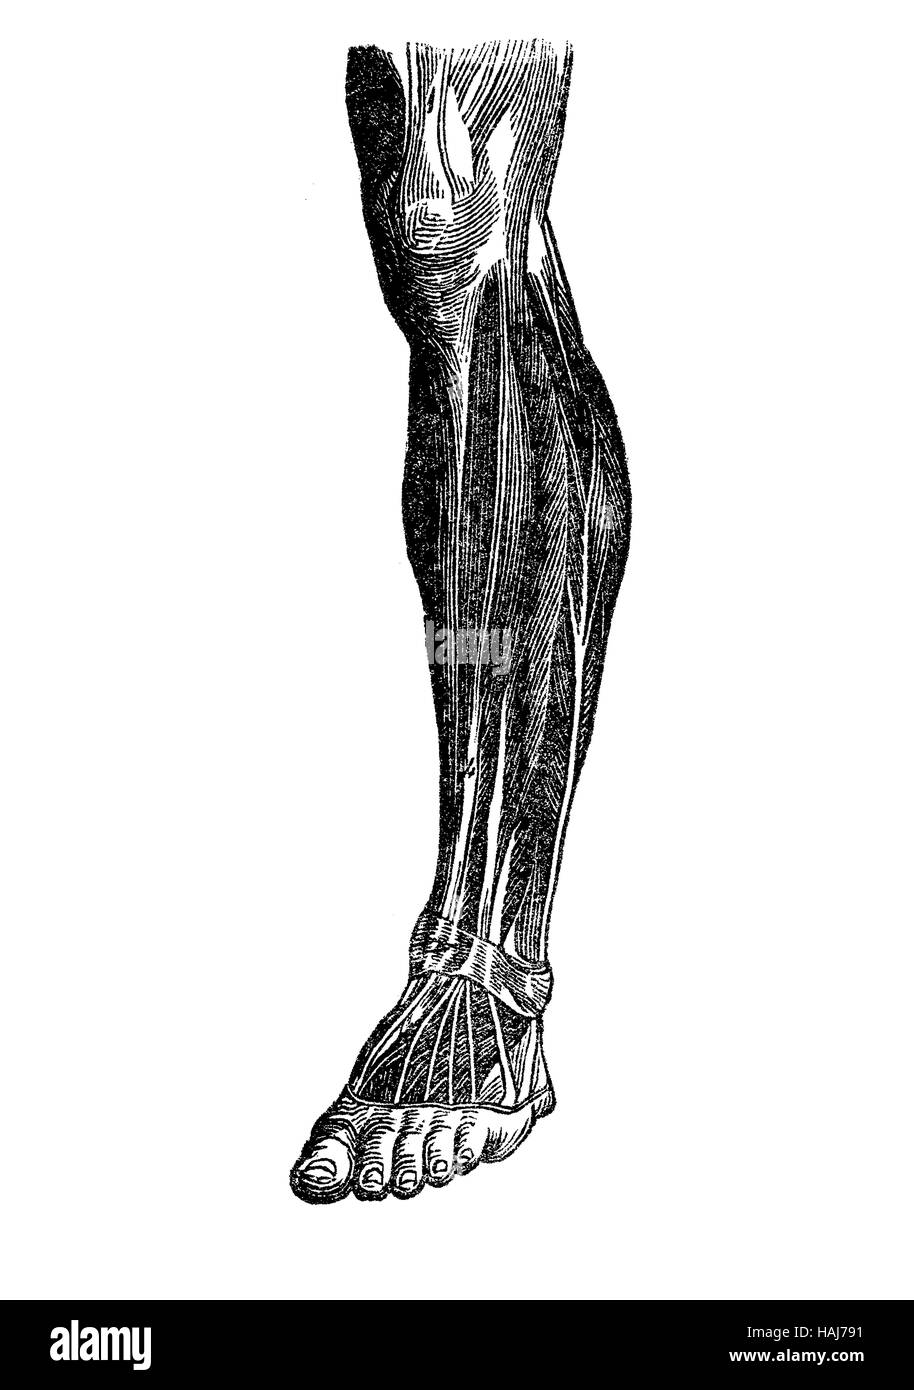

Anatomy, human musculature; foot, shank,knee Stock Photohttps://www.alamy.com/image-license-details/?v=1https://www.alamy.com/stock-photo-anatomy-human-musculature-foot-shankknee-127020013.html

Anatomy, human musculature; foot, shank,knee Stock Photohttps://www.alamy.com/image-license-details/?v=1https://www.alamy.com/stock-photo-anatomy-human-musculature-foot-shankknee-127020013.htmlRFHAJ791–Anatomy, human musculature; foot, shank,knee